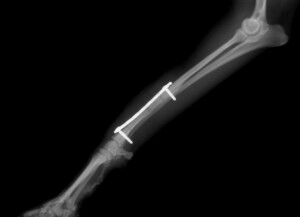

治療はプレートで固定する方法を行いました。骨折位置が橈骨先端に比較的近い位置だったことと、トイ・プードルは骨の増生が悪いことで有名なので少し気を遣う症例でした。プレートはステンレスプレートを用いました。手術直後が下の写真です。

手術後1か月は外固定で補助します。その後、レントゲンで問題ないことを確認し外固定を外しました。外した後は普通に歩行し、散歩なども普段通りにしてもらいます。獣医師によってはプレートを残したままにすることがありますが、中にはプレート部分の骨が細くなってしまうことがあります。もし仮にプレートが折れてしまった時には大変な手術が必要になることがあります。当院では高齢犬であればプレートを残したままにするのですが、この症例は若かったので上記の心配もありますので、プレートを除去することにしました。ただトイ・プードルは骨の増生が良くないことが多いので、プレートを外した直後に再骨折したということがよくあります。ですので、当院ではプレートを留めているスクリューを段階的に外していきます。下の写真は手術後3か月の時に一部のスクリューを取った写真です。